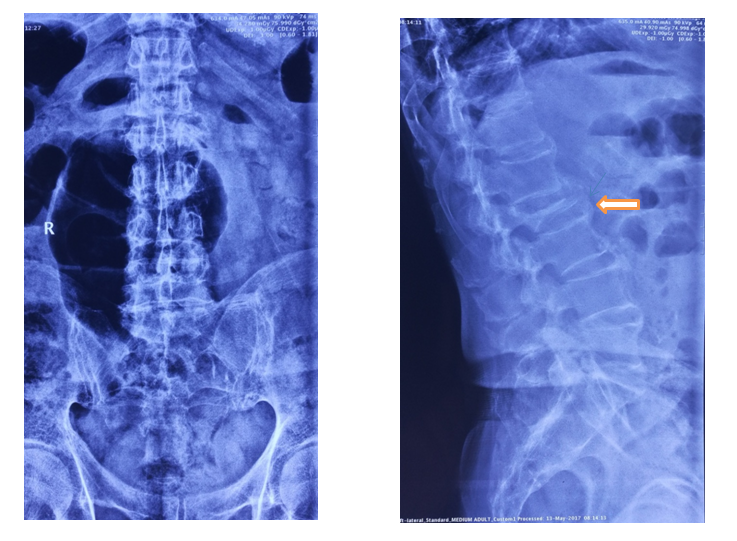

术前X线

俯卧过伸位片

术后X线

术前后侧位

术后3月X光